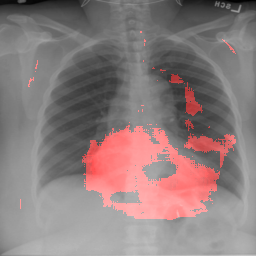

4.2.1 Cardiomegaly Localization

The localization of abnormalities in cardiomegaly examples are shown in Fig. 7. Here, of the image area is shown which has the highest sensitivity. It can be observed from the figures that the network is indeed most sensitive to the region where the heart is larger than a normal heart. We have performed this experiment on cardiomegaly and normal images and found this localization to be consistent for most examples. There is not much functional difference between a normal and cardiomegaly example other than the fact that the heart in cardiomegaly is larger than a normal heart. Given the fact that the normal images could also have various size of heart depending on the age or physical attributes of a patient, we found this level of localization sensitivity to be remarkable. Also interesting is the fact that the standard rule based features like CTR and CTAR take into account the relative size of heart and lung to determine if there is cardiomegaly present or not. In the DCN localization experiment, we see counter-intuitively that most of the signals contributing to the softmax score are coming from the heart only. This means that there are characteristic features in the shape of the heart and its surrounding regions that alone is sufficient to detect cardiomegaly. The lung and its relative size are probably less important features when trying to detect cardiomegaly. This observation is counterintuitive and needs to be explored further in future work.

8 Additional Examples of Localization

In this section we show more examples of localization. Few localization samples are shown in Fig. 11. It can be observed that, in the CXRs with Cardiomegaly (Fig. 11(a) and (b)) a fine localization around the heart is observed. In the normal CXRs (Fig. 11(c) and (d)) such localization is not observed. Rather the lowest probabilities are spread out in the CXR image. It is interesting to note that, the localization algorithm gets low probability where the heart is enlarged during cardiomegaly, but the proportion is small compared to the localization in other areas of normal CXRs. In order to observe the performance of the heat map we computed histograms of heat maps of each of the 100 CXRs in the test set for Cardiomegaly detection and average histograms are shown in Fig. 11(e) and (f) for CXRs with Cardiomegaly and normal CXRs, respectively. It is to be noted that, the histograms include both success and failure cases. It can be observed that, for CXRs with Cardiomegaly the classifier is highly sensitive toward Cardiomegaly detection even under occlusion. This indicates that, the classifier primarily looks for local features in a CXR instead of some feature that is spread out in the entire CXR. However, the classifier is not sensitive toward normal CXRs under occlusion. Rather, the probabilities are spread out in the probability spectrum. After that, we analyzed the failure cases where the classifier is unable to classify the image correctly. Two such examples of failure cases are shown in Fig. 12. The localized CXR shown in Fig. 12(a) contains Cardiomegaly whereas the classifier detects it as normal. However, the localization shows that it localizes around heart quite well despite the in accurate classification. On the other hand, Fig. 12(b) shows an example of normal image which has been classified as Cardiomegaly by the classifier. There is stronger localization around the hear that that is observed for normal images as in Fig. 11(c) and (d), however, like those images the localization is spread out.